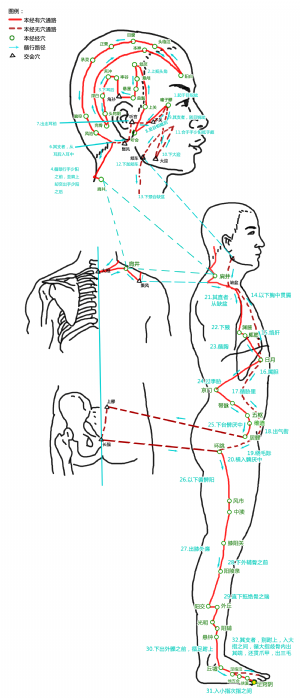

足竅陰爲經穴名(zúqiàoyīn GB44)[1]。出《黃帝內經靈樞·本輸》。《黃帝內經靈樞·本輸》原名竅陰,《聖濟總錄》名足竅陰。屬足少陽膽經[1]。足竅陰是足少陽膽經的井穴,五行屬金[1][2]。足即足部,竅即孔竅,陰爲陽之對,開竅於耳目的腎和肝均屬陰髒,此穴在足部,善治耳目諸疾,故名足竅陰[2]。足竅陰穴主治頭、五官、胸脅等疾患:如頭痛,眩暈,目痛,耳鳴,耳聾,喉痹,口於,舌強,舌本出血,熱病脅痛,咳逆,煩心,夢魘,手足轉筋,肘不得舉,癰疽,耳赤腫痛,咽喉腫痛,熱病,失眠,脅痛,月經不調,目赤腫痛,足跗腫痛,多夢,現代又用足竅陰穴治療肋間神經痛,高血壓,胸膜炎,乳腺炎,偏頭痛,目眩,神經性頭痛,神經衰弱,腦血管病後遺症,足踝腫痛,結膜炎,哮喘等。

竅,有空隙之義。陰,陰、陽之陰。竅指空孔。《黃帝內經素問》說:“肝開竅於目,腎開竅於耳,心開竅於舌,肺開竅於鼻,脾開竅於口。”此五臟皆屬陰髒。該穴所主治目疾、耳聾、舌強、鼻塞、口中惡苦諸疾與頭竅陰相類,《黃帝內經靈樞·根結》:“少陽根於竅陰,結於窗籠,窗籠者耳中也。”此穴位人體最下,在足第4趾外側趾甲角根旁1分處,爲足少陽脈氣所發之地,猶如井泉,故名足竅陰。[3]

標準定位:足竅陰穴在足第4趾末節外側,距趾甲角0.1寸(指寸)[4]。

足竅陰穴位於足趾,第四趾末節外側,趾甲根角側後方0.1寸(指寸),伸足取穴[4]。

足竅陰穴在趾端的位置

足竅陰穴在趾端的位置